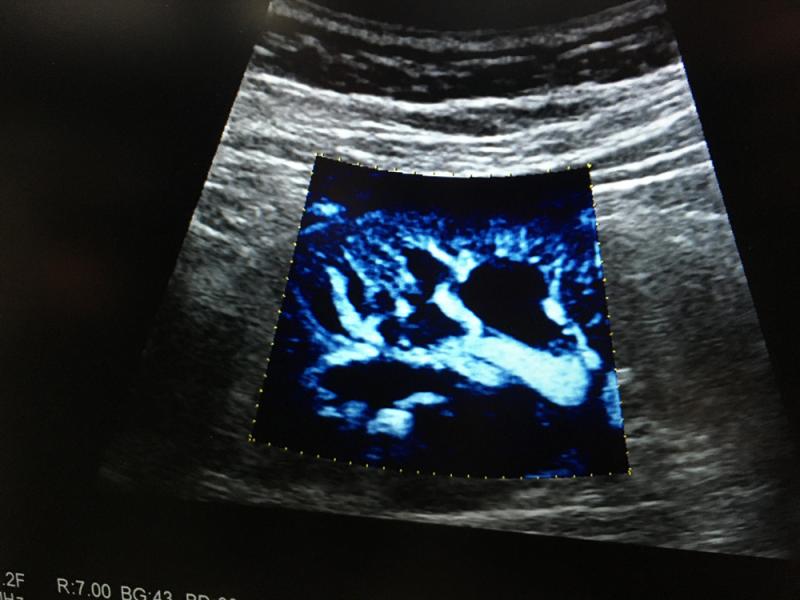

Here are images of some of the newest new medical imaging technologies displayed on the expo floor at the Radiological Society of North America (RSNA) 2019 meeting. Use the slider images below to see the photos.